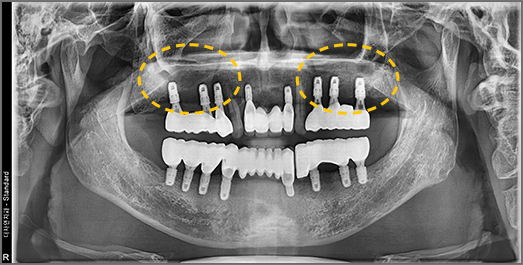

• BEFORE: 2022.12.15

• AFTER: 2023.02.23

Full-Mouth Implant Restoration

Implant treatment for comprehensive full-arch restoration

This implant option is chosen to fully restore dental function. When missing teeth have been left untreated for an extended period,

the alveolar bone volume in both the maxilla and mandible is often insufficient. Therefore, a precise surgical plan must be established

with careful consideration of each patient's overall health condition.